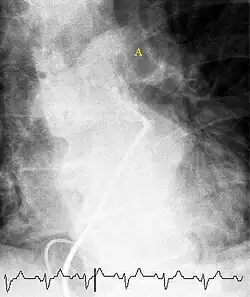

Ventilation/perfusion scan

(A) After inhalation of 20 mCi of Xenon-133 gas, scintigraphic images were obtained in the posterior projection, showing uniform ventilation to lungs.

(B) After intravenous injection of 4 mCi of Technetium-99m-labeled albumin, scintigraphic images are shown here in the posterior projection. This and other views showed decreased activity in multiple regions.

A ventilation/perfusion scan (or V/Q scan or lung scintigraphy) shows that some areas of the lung are being ventilated but not perfused with blood (due to obstruction by a clot).[19] This type of examination is as accurate as multislice CT, but is less used, due to the greater availability of CT technology. It is particularly useful in people who have an allergy to iodinated contrast, impaired kidney function, or are pregnant (due to its lower radiation exposure as compared to CT).[66][67][68] The test can be performed with planar two-dimensional imaging, or single-photon emission computed tomography (SPECT) which enables three-dimensional imaging.[59] Hybrid devices combining SPECT and CT (SPECT/CT) further enable anatomic characterization of any abnormality.[69]